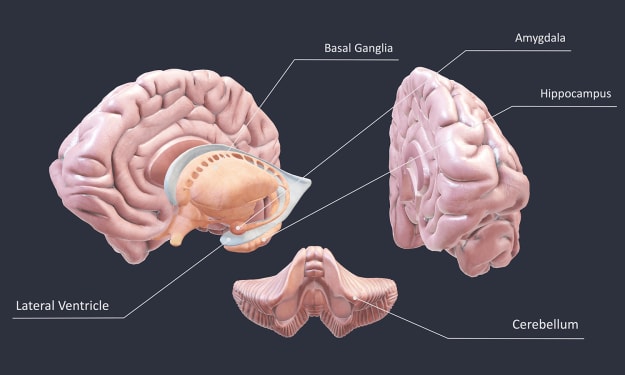

Oh no, Brain !!!

Title: The Complexities of Brain Function: Insights from Language Impairment and Recovery Introduction: The human brain is a remarkable organ that governs our thoughts, emotions, and behaviors. Its intricate structure and specialized regions allow us to process information, communicate, and interact with the world around us. Studying the brain and its functioning is crucial in understanding various neurological conditions, such as language impairments. In this article, we explore the fascinating case of James, who experienced a stroke and developed Broca's aphasia, and how his recovery sheds light on the remarkable adaptability of the brain.

HOW ?

Exploring the Intricacies of the Human Brain: An In-depth Tour Introduction (100 words): The human brain is an incredibly complex organ that governs our thoughts, emotions, and actions. In this article, we will take a detailed journey through the different regions and structures of the brain, unraveling its mysteries along the way. By understanding the anatomy and functions of various brain components, we can gain valuable insights into how our brain processes information and orchestrates our daily lives. So, let's embark on this fascinating exploration of the anterior and posterior aspects of the brain, and delve into the significance of each structure we encounter.